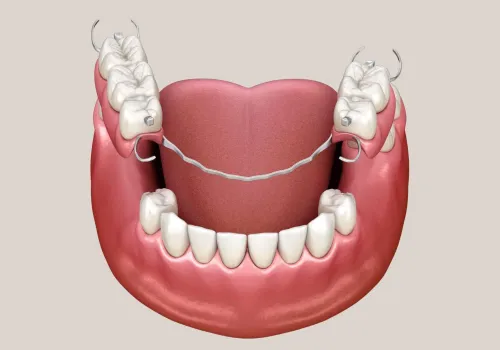

Das ALL-ON-4® Verfahren (auch bekannt als Pro Arch oder „Tooth in 1 Hour“ / „feste Zähne in einer Stunde“) wenden wir bei Patienten an, die in einem oder beiden Kiefern zahnlos sind oder nur noch wenige stark beschädigte Zähne haben. Diese Patienten leiden oft unter dem Einfluss von unschönen Prothesen auf ihr Aussehen oder können nicht alles essen, was sie möchten, da schlecht sitzender Zahnersatz oder lockere Zähne dies verhindern.